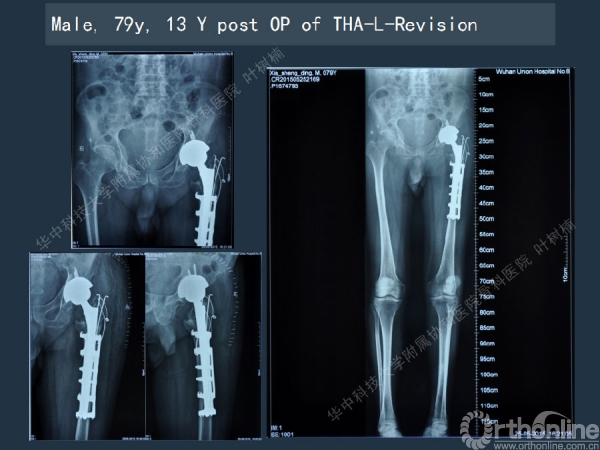

股骨侧翻修